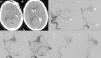

Las malformaciones arteriovenosas (MAV) cerebrales múltiples son poco frecuentes y la mayoría de las publicaciones existentes presentan casos clínicos aislados. Su incidencia en grandes series de MAV oscila entre el 0,3 y 9%, y en la mayoría de casos aparecen asociadas con otras anomalías vasculares del cerebro u otros tejidos. Presentamos el caso clínico de una mujer de 62 años que sufrió una hemorragia parenquimatosa temporal izquierda y que en los estudios neuro-radiológicos se evidenciaron 3 MAV localizadas en: lóbulo temporal izquierdo, hemisferio cerebeloso izquierdo y lóbulo temporal derecho. Las lesiones fueron tratadas con radiocirugía.

Multiple cerebral arteriovenous malformations (AVMs) are thought to be exceedingly rare lesions and have usually been reported as single cases. The incidence of multiple cerebral AVMs in major series ranges from 0.3% to 9% and, in the majority of cases, these malformations are associated with other vascular anomalies of the brain or soft tissues. We report a 62-year-old woman that presented with a left temporal haemorrhage. Angiography showed 3 AVMs located in the left temporal lobe, left cerebellar hemisphere and right temporal lobe. The lesions were treated with radiosurgery.